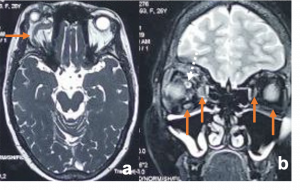

Traumatic carotid-cavernous fistula) Axial T2WI MRI of right orbit showing dilated superior ophthalmic vein along its whole course (orange arrow) b) Coronal T2WI MRI showing dilated superior ophthalmic vein (white dotted arrow) with engorgement of the extra ocular muscles compared to the contralateral normal side (orange arrows) |